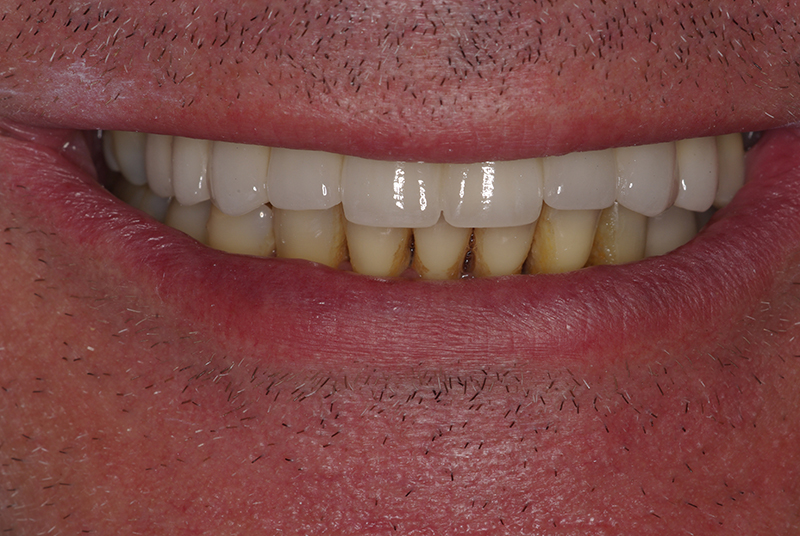

Na Clínica Pontes Odontologia, somos referência em implantes dentários em Fortaleza, oferecendo tratamentos de alta qualidade e tecnologia de ponta. Os implantes dentários são estruturas de titânio posicionadas cirurgicamente no osso maxilar ou mandibular para substituir as raízes dos dentes ausentes. Essa técnica permite a fixação de próteses personalizadas, restaurando a função mastigatória, a estética e a autoestima dos nossos pacientes.

Nosso compromisso é oferecer um tratamento de excelência, com profissionais especializados e tecnologia de última geração para implantes dentários em Fortaleza. Venha nos visitar e descubra por que a Clínica Pontes Odontologia é referência em implantes dentários em Fortaleza, devolvendo sorrisos e qualidade de vida aos nossos pacientes.